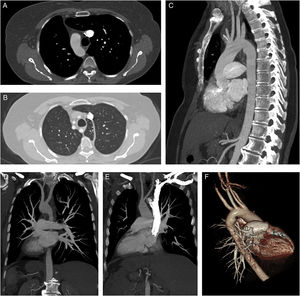

(A) Axial CT scan (mediastinal window) shows right-sided aortic arch. (B) Axial CT scan (parenchymal window) reveals a variant azygos lobe on the left hemithorax and aberrant left subclavian artery. (D and E) Coronal plan MIP CT images show total transposition of visceral organs accompanied with dextrocardia. (C, D and F) Sagittal, coronal and posterolateral projection 3D CT images show aberrant left subclavian artery originated from the distal of the right aortic arc. (E) Coronal MIP CT scan reveals origination and trace of the right and left carotid arteries.

A 57-year-old female patient presented to our hospital with complaints difficulty in swallowing and coughing over the past 3 months. There was no history of fever, vomiting, nausea, or weight loss. She did not report any similar episode in the past. Chest X-ray showed the presence of dextrocardia. Contrast enhanced computed tomography (CT) scan was performed for detailed evaluation the hearth and mediastinal structures. The contrast enhanced CT examination showed aberrant left subclavian artery, right-sided aortic arch with dextrocardia, and variant azygos lobe on the left hemithorax (Fig. 1A–F). The aberrant left subclavian artery originated from the distal of the aortic arc was coursing through to posterior of the oesophagus. On the CT scan was seen total transposition of visceral organs so was confirmed that the patient have situs inversus totalis (Fig. 1D and E). All of visceral organs were seen on mirror image of normal locations. Situs inversus totalis is a rare congenial malformation that is incidentally detected in radiological evaluations. It is known as total transposition of abdominal and thoracic organs. Right sided aortic arch results from regression of the left dorsal aorta in embryologic development.1 If the aberrant left subclavian artery is found with the right-sided aortic arch, it is the last branch of the right-sided aortic arch. Although right sided aortic arch may be related to aberrant left subclavian artery,2 coincidence of situs inversus totalis and azygos lobe variant is extremely rare. Right aortic arch with aberrant left subclavian artery may be accompanied dextrocardia. Azygos lobe is a rare anatomic variant of right apical lobe,3 but on our case it was seen on left side because of situs inversus.